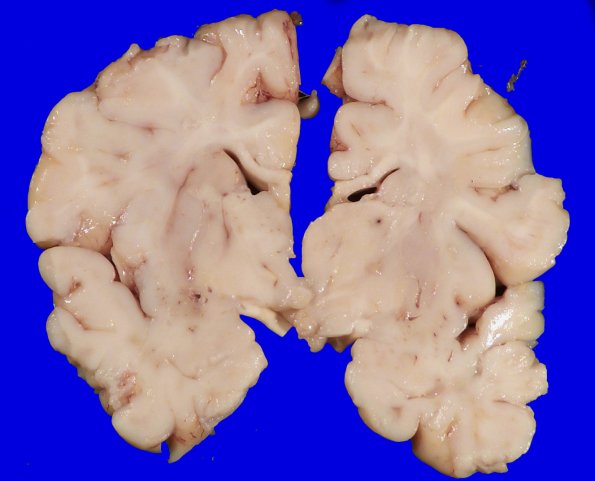

At autopsy the patient showed hepatosplenomegaly, pulmonary congestion, consolidation with right lower lobe infarct, and accelerated thymic involution. The patient’s unfixed brain weighed 560g. ---- 4A1,2 Coronal sections of the fixed brain show well preserved cortex and deep gray with a hint of white matter discoloration.